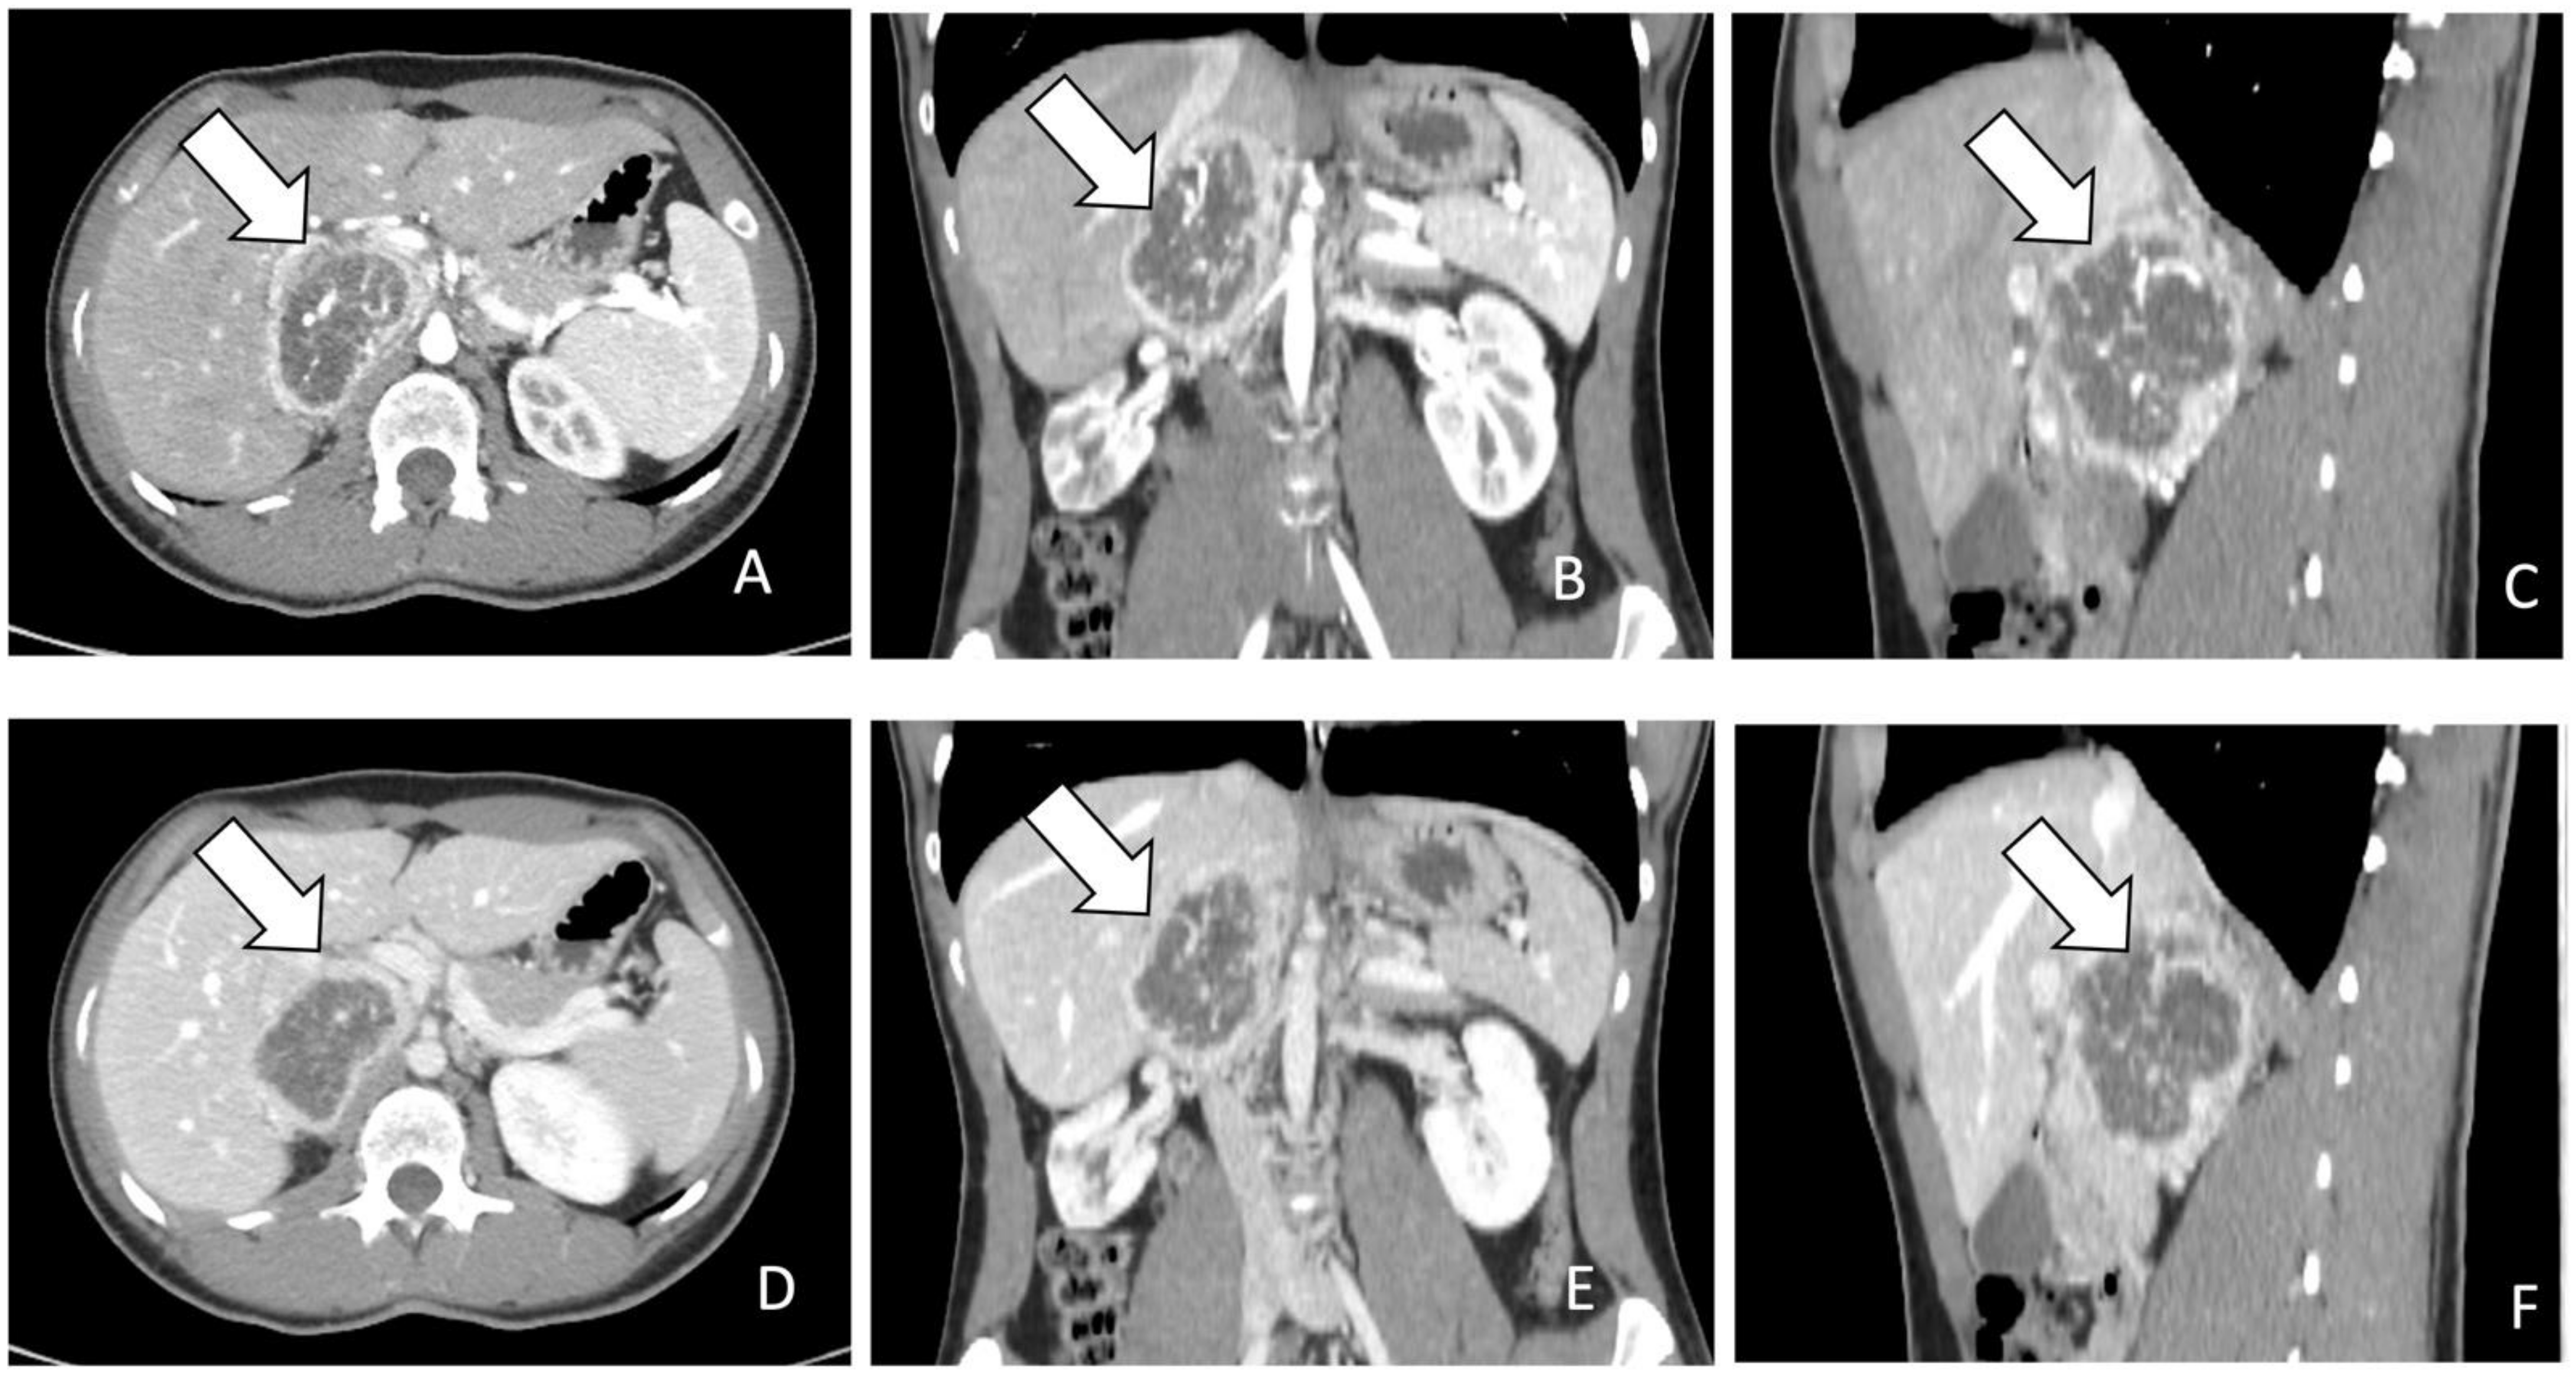

Radiologically, PPGLs are usually solid, hypervascular, and well-circumscribed masses, with sizes varying from 1 to 15 cm. Larger tumors may exhibit central necrosis, while smaller ones typically display a uniform appearance. Moreover, certain PPGLs may simulate adenomas due to macroscopic fat or may exhibit high attenuation due to hemorrhage or calcifications [6,14,21,24,25,27,31] (Figure 1).

Figure 1.

(A–F): (A). CT images in axial plane during arterial phase of contrast study. The lesion indicated by the arrow appears as a heterogenous mass with rim enhancement. (B,C). MPR post processing in coronal and sagittal planes during arterial phase. (D). CT images in axial plane during portal phase of contrast study. The lesion indicated by the arrow appears heterogenous with rim enhancement and without progressive contrast enhancement. (E,F). MPR post processing in coronal and sagittal planes during portal phase.

For the screening of PCCs, CT scan shows a high sensitivity (almost 100%) but a low specificity (50%) [11]. On CT scan, PCCs are generally more than 10 Hounsfield units (HU) with a marked enhancement that can be heterogenous due to degenerative changes [12,31] (Figure 1). Differential diagnosis with the less common lipid-poor adenomas may be challenging as they also have more than 10 HU and show similar absolute and relative percentages washout values [31].